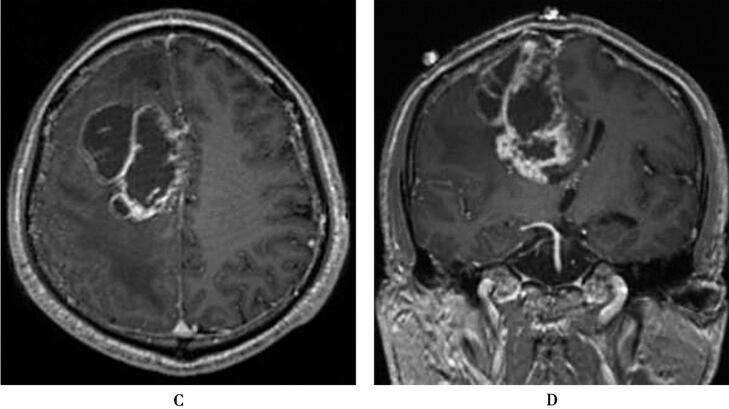

图1 大脑浆细胞瘤

右侧额叶形状不规则的异常信号灶,占位效应明显,周围脑组织广泛水肿,增强后病灶呈“花环样”不均匀强化,周围水肿区域无明显强化